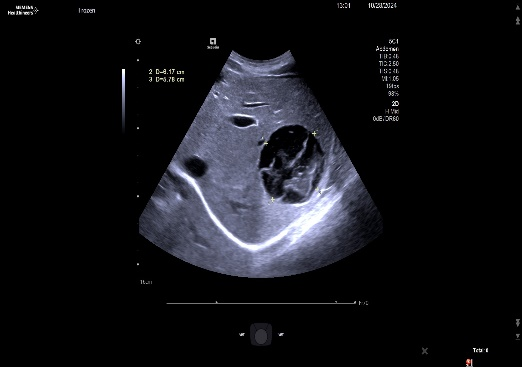

关注近日,阿里地区人民医院迎来了一项重大突破:成功为一名28岁女性患者实施了首例肝包虫病手术。患者体重40Kg,身高140cm,BMI指数为20,因“体检发现肝包虫5年,肝区疼痛1年”入院。经过B超和上腹部增强CT检查,诊断为肝囊型包虫病(CE₃型),肝脏S3段和S6、7段分别发现8×7cm和9×8cm的囊性病灶。

11月19日,手术团队在术中联合控制中心静脉压,采用Pringle法间断阻断肝门,精准定位外囊与肝组织的界限,成功避免了损伤门脉分支及胆管等重要结构,保持囊壁完整性。术中出血仅约100ml,成功完成了“肝左叶S3切除,右叶包虫外囊摘除术”。术后患者恢复良好,病理报告显示外囊完整囊性肿物,内有粉皮样物,符合包虫病特征。